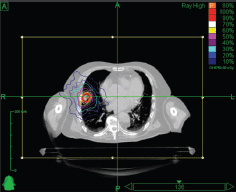

Stereotactic body RT (SBRT) is very much a technology-driven treatment modality [57]. SBRT systems are capable of producing very conformal treatment plans with a steep dose gradient outside the target. This technique makes possible safe and efficacious treatment across a broad array of anatomic locations, in proximity to critical organs, and even adjacent to or within prior RT fields. Essential requirements for SBRT are the accuracy of target delineation (see ‘Tumour Localisation in Treatment Planning’ section), and the implementation of inter- and intra-fraction tumour motion compensation strategies (especially for tumours in the lung and in the upper abdomen). The wider availability of in-room imaging and advanced treatment delivery systems means that more institutions are now offering SBRT (see ‘Tumour Localisation in Treatment Delivery’ section) [58]. At present, there are a variety of systems available for SBRT. Some of them are based on the traditional LINAC gantry, for example, Versa HD (Elekta, AB, Stockholm, Sweden) [59] and TrueBeam STx (Varian Medical Systems, Inc., Paolo Alto, CA, USA) [60], whereas others have moved away from this design in search of greater non-coplanar beam arrangements, for example, CyberKnife® (Accuray, Inc., Sunnyvale, CA, USA) [61] and VERO (Mitsubishi Heavy Industries, Ltd., Japan, and BrainLAB AG, Feldkirchen, Germany) [62, 63]. An example of a stereotactic treatment plan delivered with CyberKnife® for early-stage non-small cell lung carcinoma is shown in Figure 3.

Figure 3. Axial view of a stereotactic treatment plan delivered with CyberKnife for an early stage non-small cell lung carcinoma.